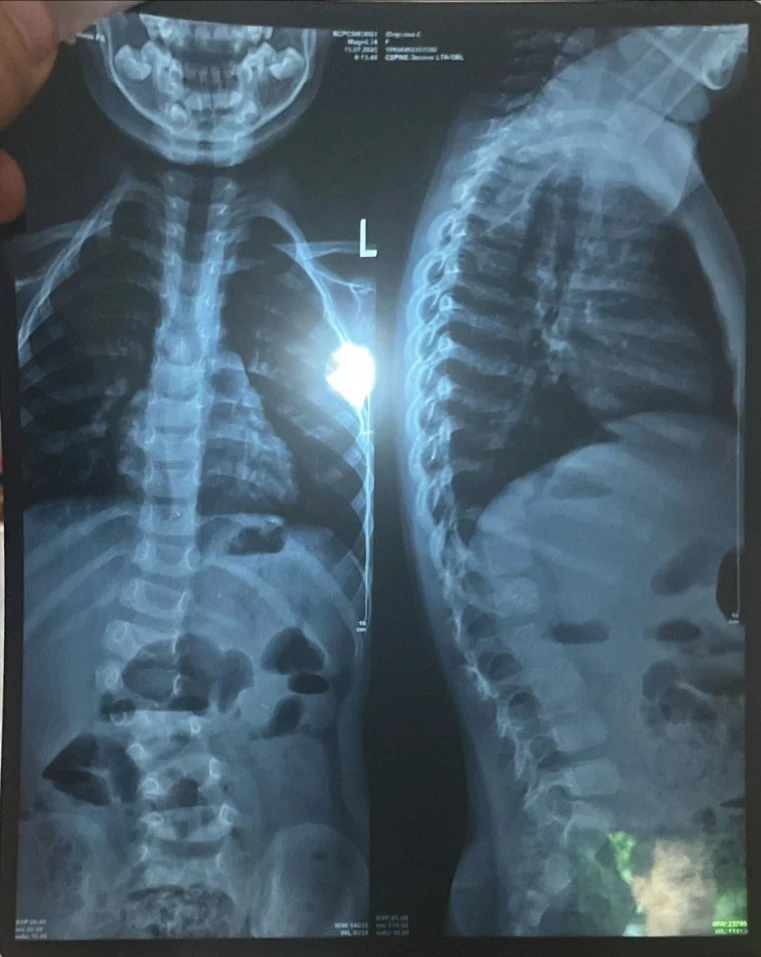

"Трудно ходить и бегать". Сумае нужна операция для исправления сколиоза

У девочки выявили сколиоз сложной формы, что вызывает у неё затруднения при ходьбе и беге, и она вынуждена проводить большую часть дня в сидячем или лежачем положении.

Сколиоз уже вызвал асимметрию тела, у Сумаи одно плечо ниже другого, а одна нога короче.